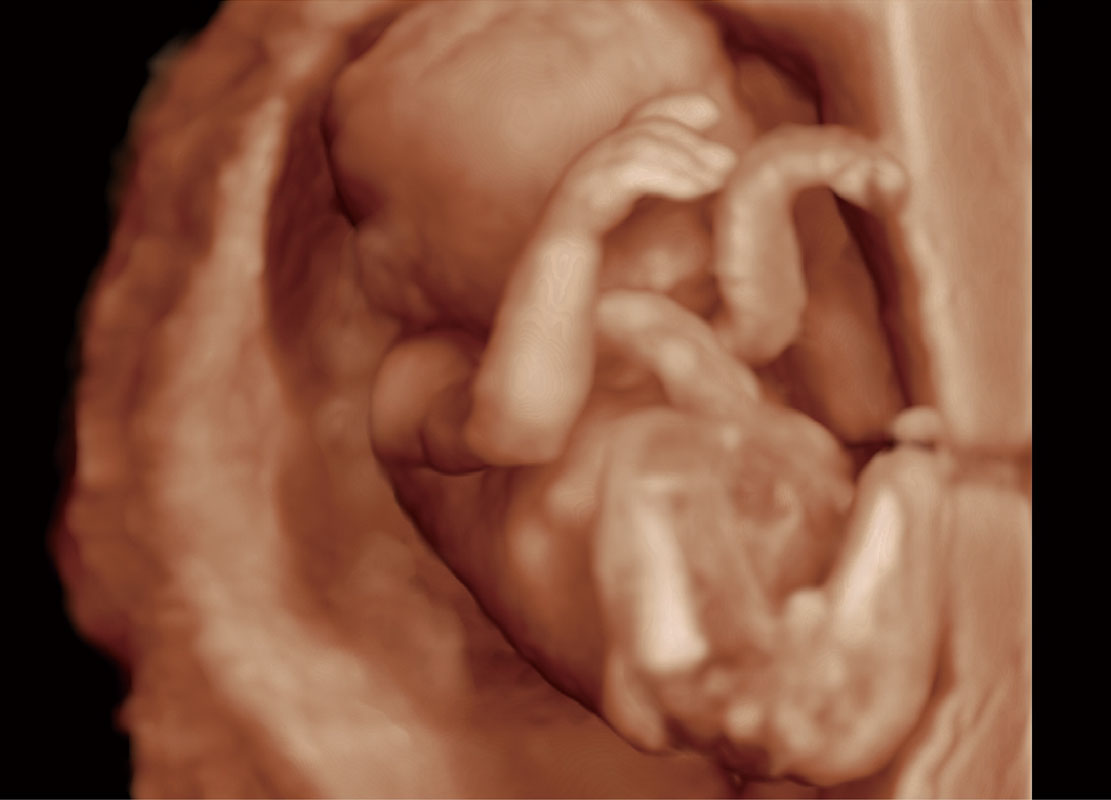

P60在胎兒早孕期超聲篩查中為您帶來(lái)優(yōu)異的圖像質(zhì)量。

高分辨率容積成像-早孕胎兒